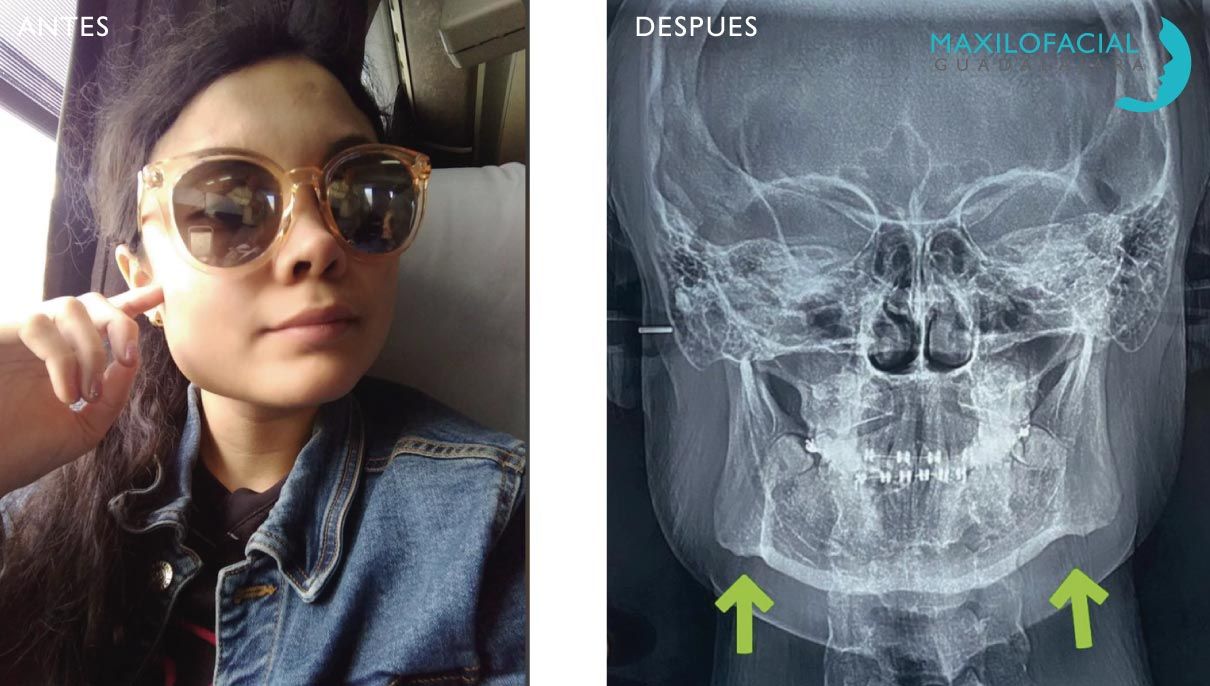

Cirugía Ortognática

Los maxilares son el asiento de los dientes y a la vez la estructura que da la forma a la cara. De ahí la necesidad de compaginar una forma estética del hueso, que conforme una buena estética facial, y a la vez una articulación correcta de los dientes, que permita una oclusión y masticación eficaz. Esta cirugía busca los dos objetivos simultáneamente la estética y la oclusión.

Si tiene una desarmonía facial y sus dientes no encajan perfectamente, consultemos para buscar la mejor forma posible de solucionar ambos problemas.

El tratamiento de estos problemas es combinado cirugía, y ortodoncia.

- Se comienza por una fase ortodoncia alineando los dientes en su lugar en relación con el hueso.

- Posteriormente se movilizan las estructuras óseas hasta su posición ideal que debe compaginar una estética correcta con una oclusión eficaz.

- Finalmente una vez estabilizada la situación ósea se completa afinando la oclusión con ortodoncia pos-quirúrgica.